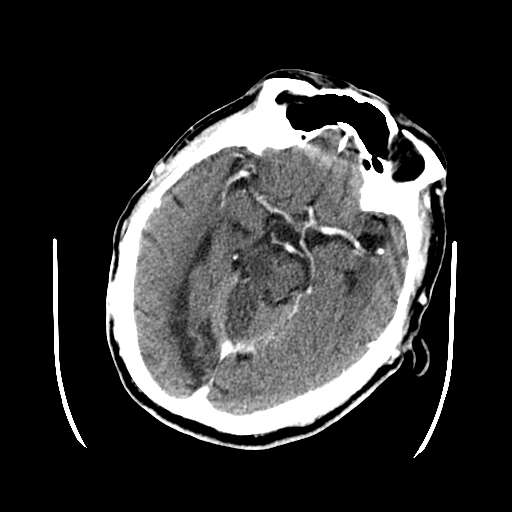

m 73

呕吐,意识障碍1小时,伴左侧偏瘫,自诉曾有过左眼视力下降。

病灶区ct值约75hu

这次病变主要是是因为脑干及小脑的梗塞,另外原有多发脑梗塞。右侧鞍上池及颞叶区可见一大部钙化的病灶,强化后略有增大,并见一条血管进入,考虑血管瘤。不排除脑膜瘤可能!~!

考虑:1、中脑右侧、右侧小脑半球、双侧丘脑缺血性脑梗塞;

2、右侧后交通动脉动脉瘤;

3、双侧基底节区腔隙性脑软化灶;

4、脑白质稀疏症。